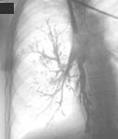

пухлина поступово звужує просвіт бронху, що викликає недостатність надходження повітря в відповідний сегмент легені і виникненню в ньому гіповентиляції. Ця ділянка на фоні повітряної легені стає менш прозора, що краще проявляється на вдиху при рентгеноскопії. При подальшому рості пухлини виникає клапанна емфізема, яка рентгенологічно краще проявляється на видиху збідненням судинного рисунка. Коли просвіт бронху повністю перекривається пухлиною розвивається ателектаз з оточуючим його запаленням (рис.1,2,3).

Справа в тому, що в ділянці легені, яка спалася, дія еластичної тяги приводить до розширення невеликих бронхів, артерій, вен та капілярів, що викликає збільшення кровонаповнення. Тому рано чи пізно в зоні ателектазу виникає запалення (рис.4). Враховуючи неспецифічність рентгенологічного зображення центрального раку легені на ранніх етапах розвитку, велике значення в діагностиці цієї форми набуває бронхоскопія, яка не тільки дає можливість встановити причину бронхостенозу, але і дозволяє отримати матеріал для морфологічного підтверждення діагнозу. Але для проведення диференційної діагностики виконують і бронхографію. Так ознаками пухлини, яка не повністю закриває просвіт бронху, на бронхограммі є дефект заповнення різної форми та довжини (в залежності від розмірів вузла та його конфігурації). При повній обтурації бронху спостерігається симптом „культі" чи „ампутації".

Рис.1 Рис.2 Рис.3

Рис.4

Рис.5 Рис.6

Рис.7 Рис.8

Рис.9